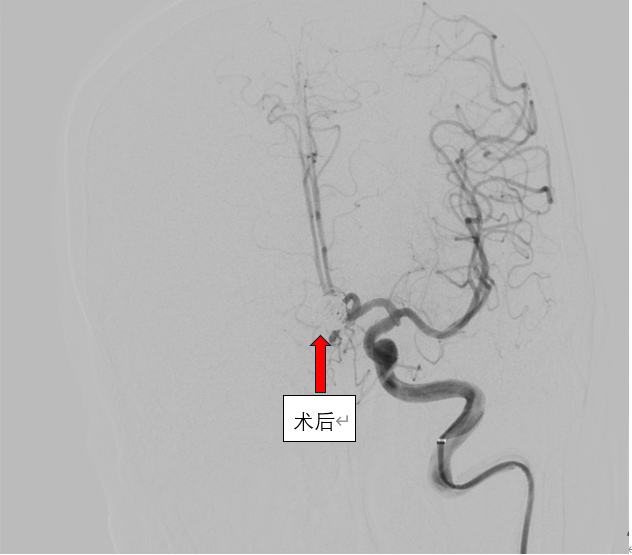

这是一场不容有失的“微雕”手术。在高精度数字减影血管造影的引导下,在介入导管室的密切配合下,介入团队犹如拥有“透视眼”,将微导管如丝般柔顺地导航至病灶处。随后,比发丝还细的铂金弹簧圈被精准、稳定地送入动脉瘤囊内,直到将那个致命的膨出部位完全填塞,血流不再涌入,破裂风险被彻底解除。手术台上,危机化解;监护室里,生命体征渐趋平稳。从命悬一线到转危为安,再到最终好转出院,这场与死神的极速竞赛,彰显了医院在急诊脑血管介入救治方面的强大实力与高效协作。

信任,是医患之间最宝贵的桥梁。一个月前,另一位患者在住院期间被查出颅内竟藏有三枚“不定时炸弹”——三个高危动脉瘤。面对如此复杂的病情,神经内科团队没有冒进,而是制定了审慎而周密的“分步拆弹”计划。首次手术,马磊主任带领团队凭借丰富的经验,成功栓塞了其中风险最高的两个动脉瘤。术后患者恢复良好,病情平稳。这份成功的体验和期间无微不至的关怀,铸就了患者及家属坚实的信任。基于此,患者本月再次满怀信心地入院,接受最后一枚动脉瘤的栓塞治疗。手术台上,团队操作愈发沉稳精准,顺利完成“收官之战”。术后患者同样病情平稳,好转出院。